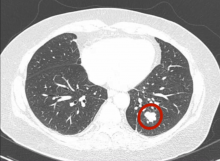

The patient was a 69-year-old woman with lung metastases from a colon adenocarcinoma, one in the right upper lobe apical segment and the other in the left lower lobe. It was proposed first to resect the right lesion by robotic assisted segmentectomy and to perform further surgery for the left side after recovery from the first operation. Ports for the camera and for the left arm were placed in the seventh intercostal space with the anterior port for the right arm placed in the sixth intercostal space. After port placement, the authors performed routine intercostal block with anesthetic solution under endoscopic vision. The dissection was started by exposing the pulmonary artery and then the upper pulmonary vein. To improve exposure, the authors remove not only the soft tissue but also all the lymph nodes at this site, promoting the lymphadenectomy. The pleura was opened over the posterior surface to expose the bronchus. After the authors obtained a good exposition of the hilum elements for the S1 segment, they started to staple the artery branch for the S1 segment. The next element to be stapled was the venous branch. The last hilum element stapled was the bronchus (B1). At this time, to help the intersegmental plane stapling, the authors injected 3 ml of a solution with ICG into the peripheral venous line. With the Firefly system turned on, the authors were able to see the margin of the S1 segment, which has its vascular supply sectioned and therefore does not stain in green. They marked the lung tissue with the Maryland bipolar forceps, then turned off the Firefly system and started to divide the intersegmental plane by stapling. Once the segment was loose, they used a bag to remove the specimen through the assistant port.